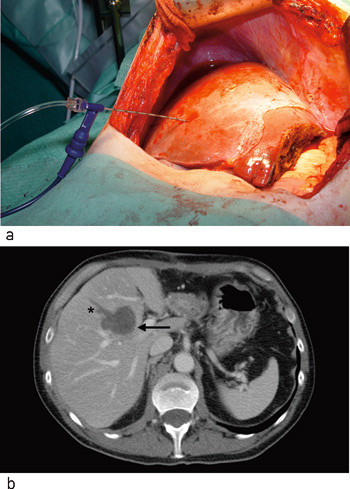

Etter avsluttet ablasjon ble vevsskaden vurdert. Ablasjonen ble ansett for å være adekvat hvis både tumor og en randsone på minst 0,5 – 1 cm rundt tumor var behandlet. Elektroden ble reposisjonert hvis tumor ikke ble oppfattet som adekvat behandlet. Det ble gjort henholdsvis to (n = 13), tre (n = 3) eller fire (n = 1) elektrodeplasseringer. Stikkanalen ble koagulert ved hver reposisjonering for å unngå implantasjonsmetastaser. Figur 2a viser en perfusjonselektrode posisjonert i en tumor. Postoperativt ses et velavgrenset område som ikke lader opp kontrastmiddel (fig 2b).